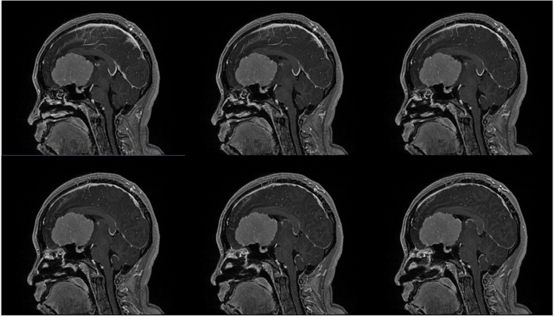

入院查体:神志清,精神可,言语流利,左侧瞳孔4mm>右侧瞳孔3.5mm,右侧对光反射存在,间接对光反射消失,左侧直接对光反射消失,间接对光反射存在,左眼失明,右侧鼻唇沟浅,四肢肌力及肌张力大致正常,双侧巴氏征未引出,颈软。

入院诊断:颅内占位病变(前颅窝底)脑膜瘤?;左眼失明;鼻炎

前颅窝底脑膜瘤常起源于前颅底筛骨筛板处的硬膜,瘤体多为双侧生长,少数为偏侧生长,女性稍多于男性。肿瘤可累及鸡冠和蝶骨平台的任何区域,是前颅窝肿瘤中最多见的一种。因为肿瘤位于前颅窝底,额叶在功能上属于“哑区”,患者就诊发现肿瘤时瘤体多已巨大。主要症状可有颅内压增高症状、视力减退、癫痫以及精神症状等。该患者主因“左眼失明10个月,头痛3个月”就诊。术中采用双额冠状开颅,左侧为主,由于肿瘤体积巨大,术中切除少许薄层额叶脑组织,边离断基底、边瘤内减压,分块切除肿瘤,最终探查肿瘤基底主要位于鸡冠、筛板、蝶骨平台、鞍结节、前床突处硬膜,术中见肿瘤供血主要来源于前颅窝底硬膜及大脑前动脉分支,术中仔细辨认供血动脉、过路血管,大脑前动脉及其分支保护完好,术中见视神经、视交叉受压明显,尤其是左侧视神经已缺血苍白,最终达Simpson II级切除。术者体会,该患者术前行多模态重建,可见瘤表数条粗大的静脉,术中切莫过早离断肿瘤的引流静脉,以防因引流不畅致瘤体肿胀出血;术前行多模态重建,利于鉴别供血动脉、过路血管,早期离断供血动脉更利于肿瘤切除;该类肿瘤基底一般较为广泛,不能盲目离断基底,尤其是近鞍结节处,可以于中线处离断基底,进入第一间隙后向两侧探查并保护视神经,待充分缩小瘤体看清楚毗邻的血管神经后再将其完全切除;术毕做好多层颅底重建以防脑脊液漏。另外,该患者术前左眼失明已达10个月,术后第1天即有光感,术后1月复查左眼视力可达50cm内数指,这在临床中非常少见,对于此类病人,不要轻易放弃挽救视力的任何机会。